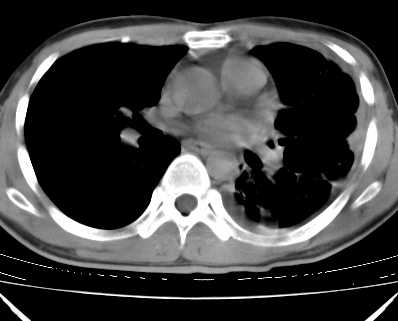

二周前患者无明显诱因出现咳嗽,多为刺激性干嗽,无咯血,伴心悸,低热,夜间无明显盗汗,消瘦明显

年龄?左侧胸腔中量积液,左下肺见有较多斑片状和大片状影,伴有支气管充气征,考虑:1、左下肺炎;2、结核。肿瘤可以基本排除。

考虑:1、左下肺结核左侧胸腔中量积液,心包积液纵隔肿大淋巴结.

考虑:1、左侧中量胸腔积液伴左肺下叶肺膨胀不全、炎症。

2、心包积液。

左下肺见有较多斑片状和大片状影,支气管通畅,左侧胸腔积液,考虑:左下肺炎伴胸腔积液

1、左侧中量胸腔积液伴左肺下叶肺膨胀不全、。

左肺舌叶及下叶见斑片状,大片状高密度影并相应处胸膜及心包不规则增厚,左肺下叶膨胀不全。右肺未见异常,双肺段以上支气管通畅。纵隔左移,其内未见明显肿大淋巴结。左侧胸腔积液。

1.考虑:左肺化脓性炎症。2.左侧胸腔积液(中等量)。3.心包炎症。